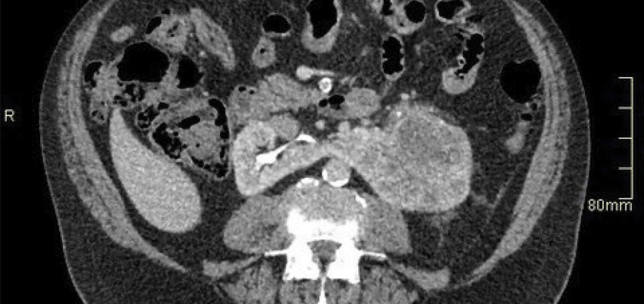

Paediatric Urology , Functional / Reconstructive Urology

Upper tract abnormalities

Functional / Reconstructive Urology

Functional and reconstructive urology